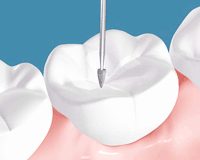

切削器具でむし歯の部分を選択的に削ります

完全にむし歯を取り終えたところです。かなり大きな穴が開いています。

削った表面に対して接着処理を行います。

ここが重要ですが、緊密にかつスムーズに詰められるように壁をつくって余計なところに流れないよう堰き止めます。この壁を作る器具の出現で、型採りが必要なレジンインレーは全く行わないようになりました。

プラズマ照射器・高出力ハロゲン照射

レジンを緊密に充填し、専用の光で確実に硬化させます。

形態修正やかみ合わせの調整を行い、表面を研磨します。